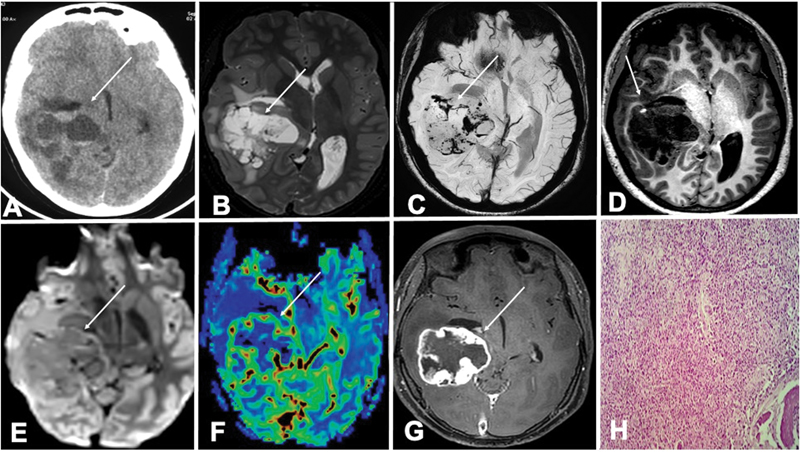

A 17-year-old female initially presented with pain and swelling in the left calf for 1 month. Initial evaluation with magnetic resonance imaging (MRI) of the lower limb ( [Fig. 1A–E]) showed a heterogeneous lesion in both T1-weighted and T2-weighted images at the left upper fibula with surrounding peripheral enhancing soft tissue lesion (70 × 63 × 63mm) and medullary changes that suggested the radiological possibility of osteosarcoma, Ewing's sarcoma, or chronic osteomyelitis. Histopathology findings on biopsy showed the tumor cell had hyperchromatic pleomorphic nucleoli with a high nuclear/ cytoplasm ratio and a moderate amount of cytoplasm. The tumor showed overall areas of necrosis (80–90%) with few areas of chondroblastic differentiation with features consistent with conventional osteosarcoma. CT chest was done for metastatic screening and found to be normal. The patient was started on neoadjuvant ifosfamide, doxorubicin, cisplatin protocol followed by surgery and adjuvant chemotherapy within 8 months. She had developed ifosfamide encephalopathy during chemotherapy post the eighth cycle, following which further chemotherapy was withheld. She was on regular follow-up, doing fine for the next year and CT chest was normal. The patient started having dull aching, right temporal headache after 1 year of the last cycle of chemotherapy for which she was evaluated with CT scan in a local hospital, which showed a neoplastic mass in the right cerebral hemisphere causing a mass effect with midline shift to the left side ([Fig. 2A]). MRI was performed after 20 days of symptom onset showed a right supratentorial mass lesion in the right posterior temporal lobe with internal bleeding and peripheral enhancement, mass effect with midline shift. The lesion was T1 hypointense with focal areas of hyperintensities, T2 hyperintense with fluid–fluid level, multiple areas of blooming on susceptibility-weighted imaging, and without restriction on diffusion-weighted imaging ([Fig. 2B-E]). Elevated perfusion was seen within the lesion and irregular shaggy enhancement on the postcontrast study ([Fig. 2F, G]). No soft ossification or calcification was seen on phase images. With these constellations of findings, an imaging diagnosis was made of high-grade glioma. The second possibility was osteosarcoma metastasis, as known primary was osteosarcoma of fibula but was confounded by the absence of other metastatic areas and no calcification within the tumor mass. She was admitted to the oncology department and evaluated with positron emission tomography-computed tomography, which showed remission in the primary carcinoma site, with no other metastatic lesion anywhere in the body. Neurosurgery opinion was taken and was they advised for surgery as the tumor was quite big with radiological features suggestive of a high-grade tumor. Right frontotemporal craniotomy and gross total excision of the tumor were done. Intraoperative findings showed an intra-axial firm to hard whitish solid cystic lesion arising from the right lateral ventricle and extending to the temporal base, invading the pial surface. The tumor was dissected circumferentially in a piecemeal fashion and excised with no gross residual disease. Histopathology of the resected lesion showed a tumor in the right lateral ventricle extending to the temporal lobe comprised of multiple firm-to-hard tissue pieces measuring 9 × 8 × 1cm. Microscopy sections examined showed that the tumor was composed of spindle cells, mitosis, and areas of necrosis with lacy osteoid formation and a few chondroblastic areas ([Fig. 2H]). The above features were suggestive of metastatic osteosarcoma. The patient was symptomatically better after the procedure, and was further planned for methotrexate, ifosfamide, and etoposide.

| Fig 1 : Magnetic resonance imaging of the calf showing the fibular osteosarcoma. Sagittal T1 (A), sagittal T2 (B), and axial T2 (C) showed heterogeneous a heterogenous lesion involving the upper end of the fibula with adjacent soft tissue components (arrow). Axial phase-contrast (PC; D) and sagittal T1 PC (E) showed peripheral enhancement with a non-enhancing internal necrotic component (arrow).